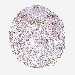

KIDNEY RENAL CLEAR CELL CARCINOMA (VALIDATION) - Interactive survival scatter ploti

The Survival Scatter plot shows the clinical status (i.e. dead or alive) for all individuals in the patient cohort, based on the same data that underlies the corresponding Kaplan-Meier plots. Patients that are alive at last time for follow-up are shown in blue and patients who have died during the study are shown in red.

The x-axis shows the expression levels (FPKM) of the investigated gene in the tumor tissue at the time of diagnosis. The y-axis shows the follow-up time after diagnosis (years). Both axes are complimented with kernel density curves demonstrating the data density over the axes. The top density plot shows the expression levels (FPKM) distribution among dead (red) and alive patients (blue). The right density plot shows the data density of the survived years of dead patients with high and low expression levels respectively, stratified using the cutoff indicated by the vertical dashed line through the Survival Scatter plot. This cutoff is automatically defined based on the FPKM cutoff that minimizes the p-score. The cutoff can be changed by dragging the vertical line or by entering a cutoff value in the square labeled "Current cut-off".

Under the Survival Scatter plot the p-score landscape (black curve; left axis) is shown together with dead median separation (red curve; right axis). Dead median separation is the difference in median mRNA expression between patients who have died with high and low expression, respectively. It is calculated as follows: median FPKM expression of dead patients with high expression - median FPKM expression of dead patients with low expression. This is intended to aid the user in visually exploring custom cutoffs and the associated p-scores and dead median separation.

Individual patient data is displayed and can be filtered by clicking on one or more of the category buttons on the top of the page. Categories describing expression level and patient information include: high, low, alive, dead, female, male and tumor stages. The scale of the x-axis can be toggled between linear and log-scale by clicking on the "x log" button. Mouse-over function shows TCGA ID, patient information and mRNA expression (FPKM) for each patient.

& Survival analysisi

Kaplan-Meier plots summarize results from analysis of correlation between mRNA expression level and patient survival. Patients were divided based on level of expression into one of the two groups "low" (under cut off) or "high" (over cut off). X-axis shows time for survival (years) and y-axis shows the probability of survival, where 1.0 corresponds to 100 percent.

S100A4 is not prognostic in Kidney Renal Clear Cell Carcinoma (validation)

Best expression cut offi

Based on the FPKM value of each gene, patients were classified into two groups and association between prognosis (survival) and gene expression (FPKM) was examined. The best expression cut-off refers the FPKM value that yields maximal difference with regard to survival between the two groups at the lowest log-rank P-value. Best expression cut-off was selected based on survival analysis .

When clicking on this number, the vertical dashed line indicating cut-off, the interactive survival plot, and the Kaplan-Meier curve will be adjusted to show results based on the best expression cut-off.

: 108.1

TCGA RNA samplesi

RNA-seq data is reported as average FPKM (number Fragments Per Kilobase of exon per Million reads), generated by the The Cancer Genome Atlas (TCGA) .

Normal distribution across the dataset is visualized with box plots, shown as median and 25th and 75th percentiles. Points are displayed as outliers if they are above or below 1.5 times the interquartile range. FPKM values of the individual samples are presented next to the box plot.

Average pTPM 173.2

Number of samples 100